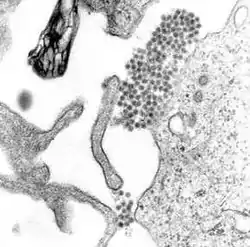

Denguefeber (el. dengue-feber) er en influenzalignende sygdom, der forårsages af denguevirus, og som er en zoonose, idet denguevirus ligesom zikavirus overføres fra myg.[1][2] Uden for troperne er dengue en ny sygdom, der rammer dele af Europa, herunder Frankrig, Italien, Portugal, Spanien og Kroatien.[3]